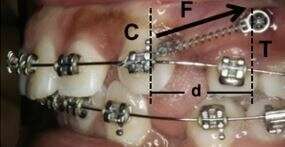

Cyclic loading (vibration) accelerates tooth movement in orthodontic patients

Clinical Experience with the Use of Pulsatile Forces to Accelerate Treatment